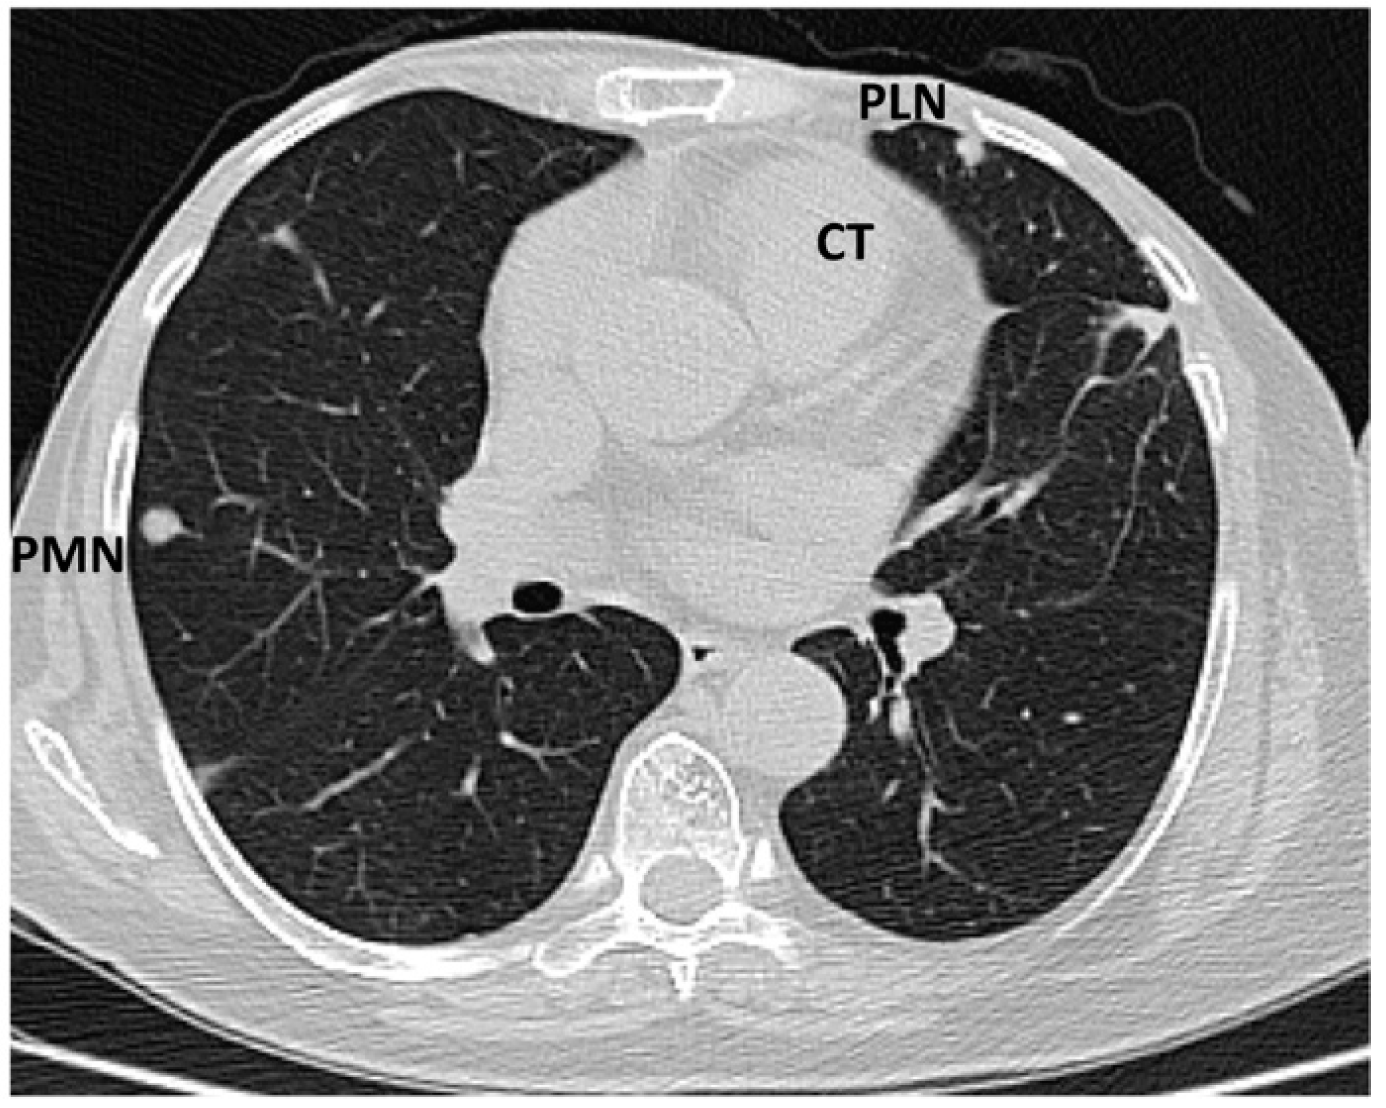

The tumour size and degree of infiltration over the whole apex of the left ventricle were determined by injecting 2 mL of SonoVue (Bracco S.p.A., Milan, Italy) at the level of intra-myocardial contrast in the left ventricle. The presence of microbubbles at this level confirmed the vascularization of the tumour mass. A non-homogeneous right ventricular mass of 88/61/80 mm extending to the left ventricle with areas of necrosis in both ventricles, disseminated lobular nodules on both pulmonary fields measuring 9 mm (right lung), 17 mm (left lung), and right para-tracheal adenopathy were identified on a thoracic CT scan (Figure 5 and Figure 6).

Figure 5. Computed tomography scan: sub-pleural peripheral nodular lesions typical of tumours (abbreviations: CT = cardiac tumour, PLN = pleural nodule, PMN = pulmonary nodule).